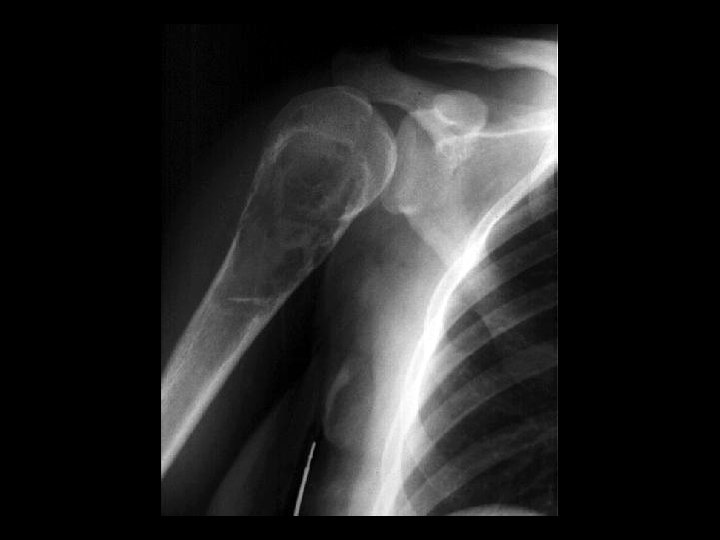

Hill-Sachs Deformity and Osseous Bankart Lesion • • • Findings: – Impaction fracture of the posterolateral humeral margin (Hill -Sachs) – Fracture of the osseous glenoid rim (Bankart) – secondary osteoarthritis Related to repeated anterior dislocations (shoulder instability) Bankart lesion is typically only of the cartilaginous labrum, best seen on MRI